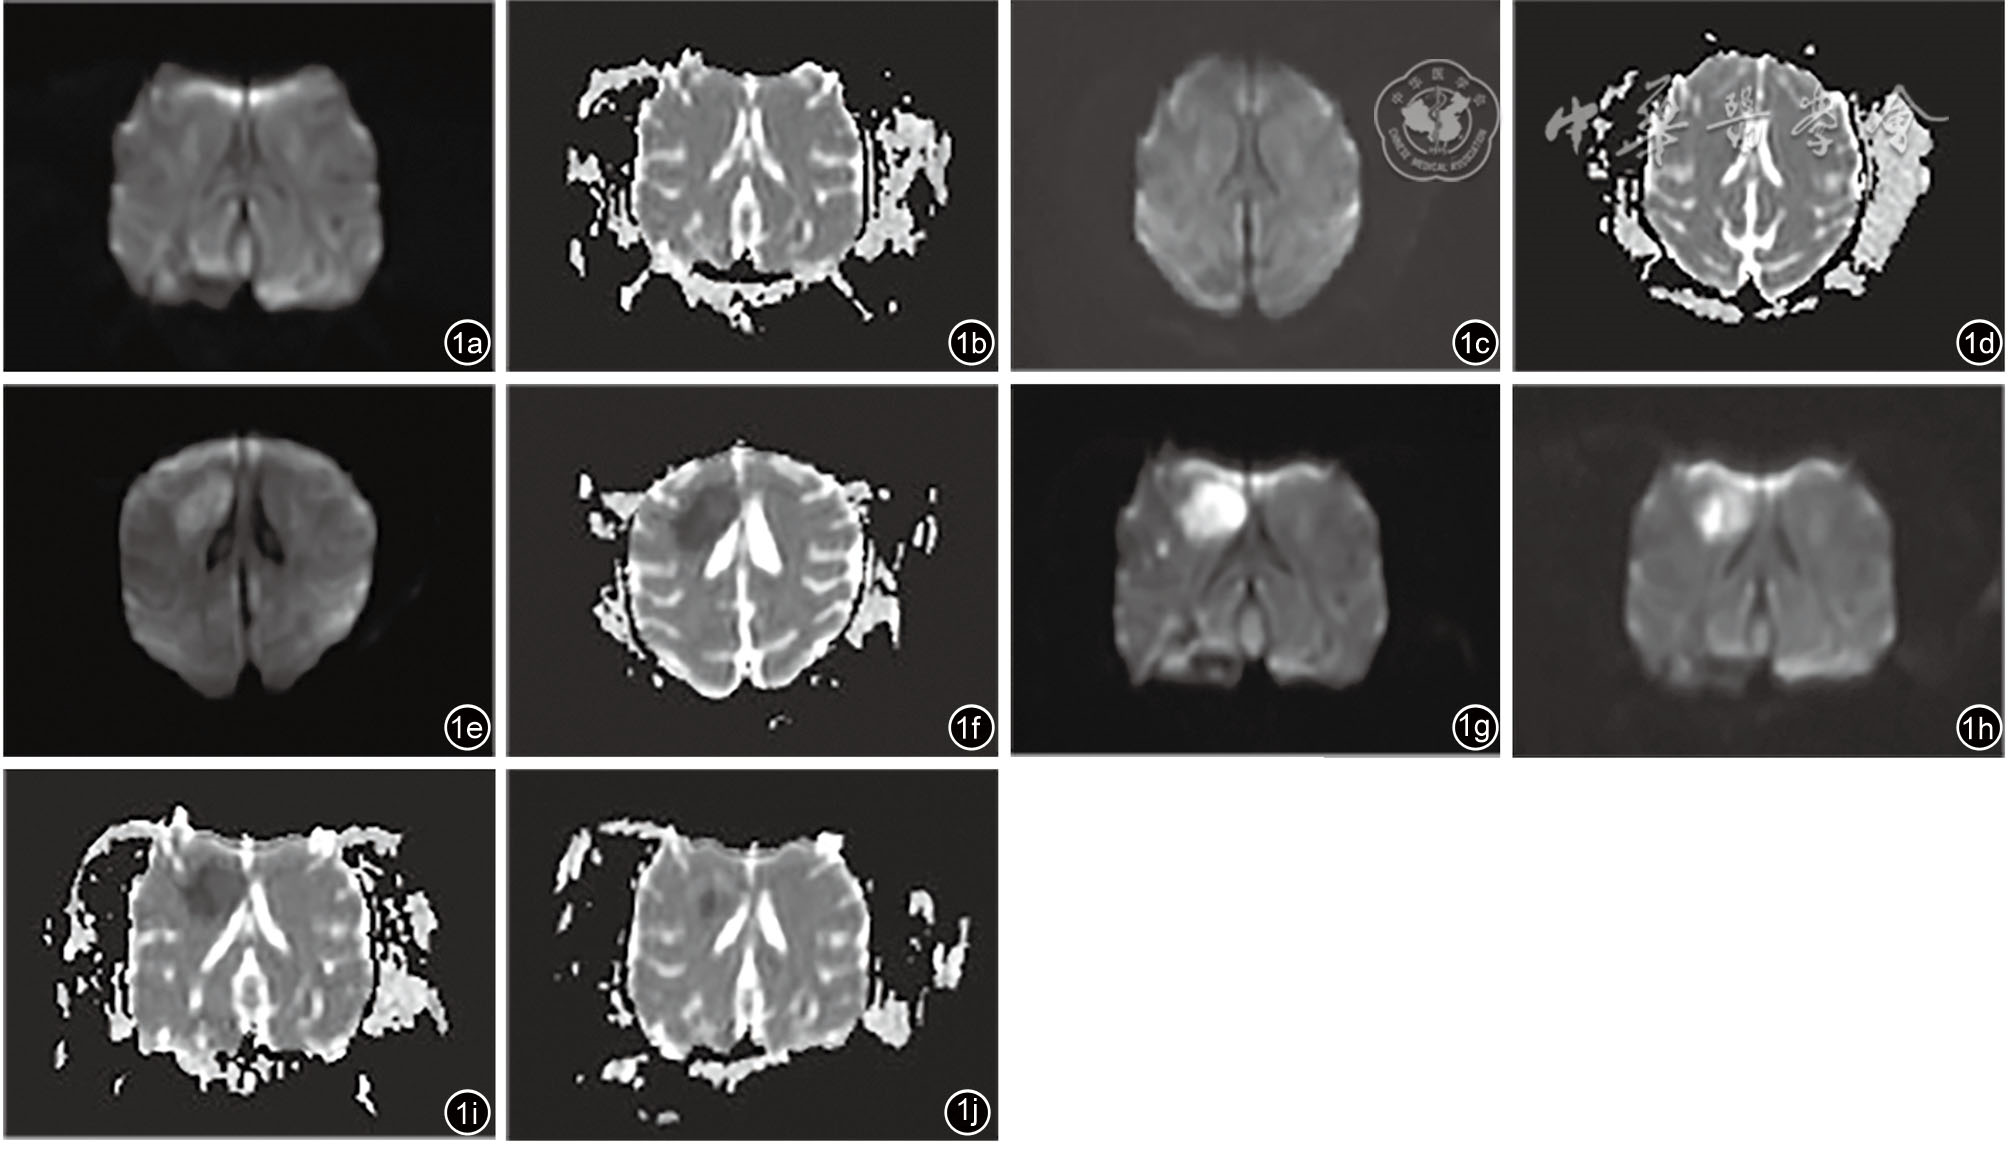

Zhang Y, Deng X, Chu J, et al. Diffusion- and perfusion-weighted imaging to detect neurological deficits in acute focal cerebral ischemia in rabbits [J]. J Integr Neurosci, 2024, 23(8): 156.

Ben RJ, Jao JC, Chang CY, et al. Longitudinal investigation of ischemic stroke using magnetic resonance imaging: Animal model [J]. J Xray Sci Technol, 2019, 27(5): 935-947.